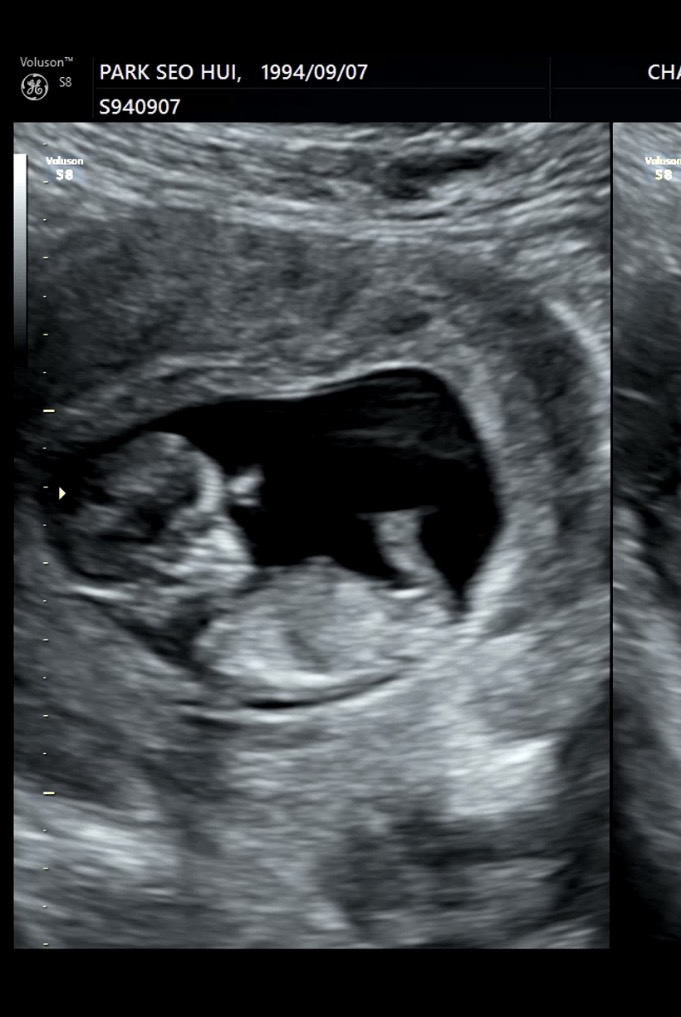

11주 6일이에요ㅠㅠ각도법문의요.ᐟ.ᐟ

11주면 아직 작아서 안보여요😂 14주는 되어야알수있어요